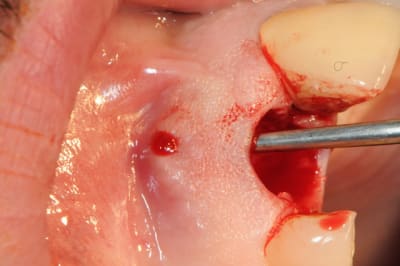

l'extraction est réalisée et on constate que la table externe est complètement détruite sur presque 1 cm .

le périoste est décollé de la table externe sur tout le pourtour de la déhiscence en passant par l'avéole de l'extraction. pas de lambeau.

une membrane est insérée entre le périoste et l'os et repose sur les bords de la déhiscence. c'est la partie la plus dificile à faire.

peu visible sur la photo, mais une fois la membrane en place, elle affleure avec le bord cervicale.

8-11 décolement du périoste de la table externe en passant par l'alvéole

12-15 insertion délicate de la membrane